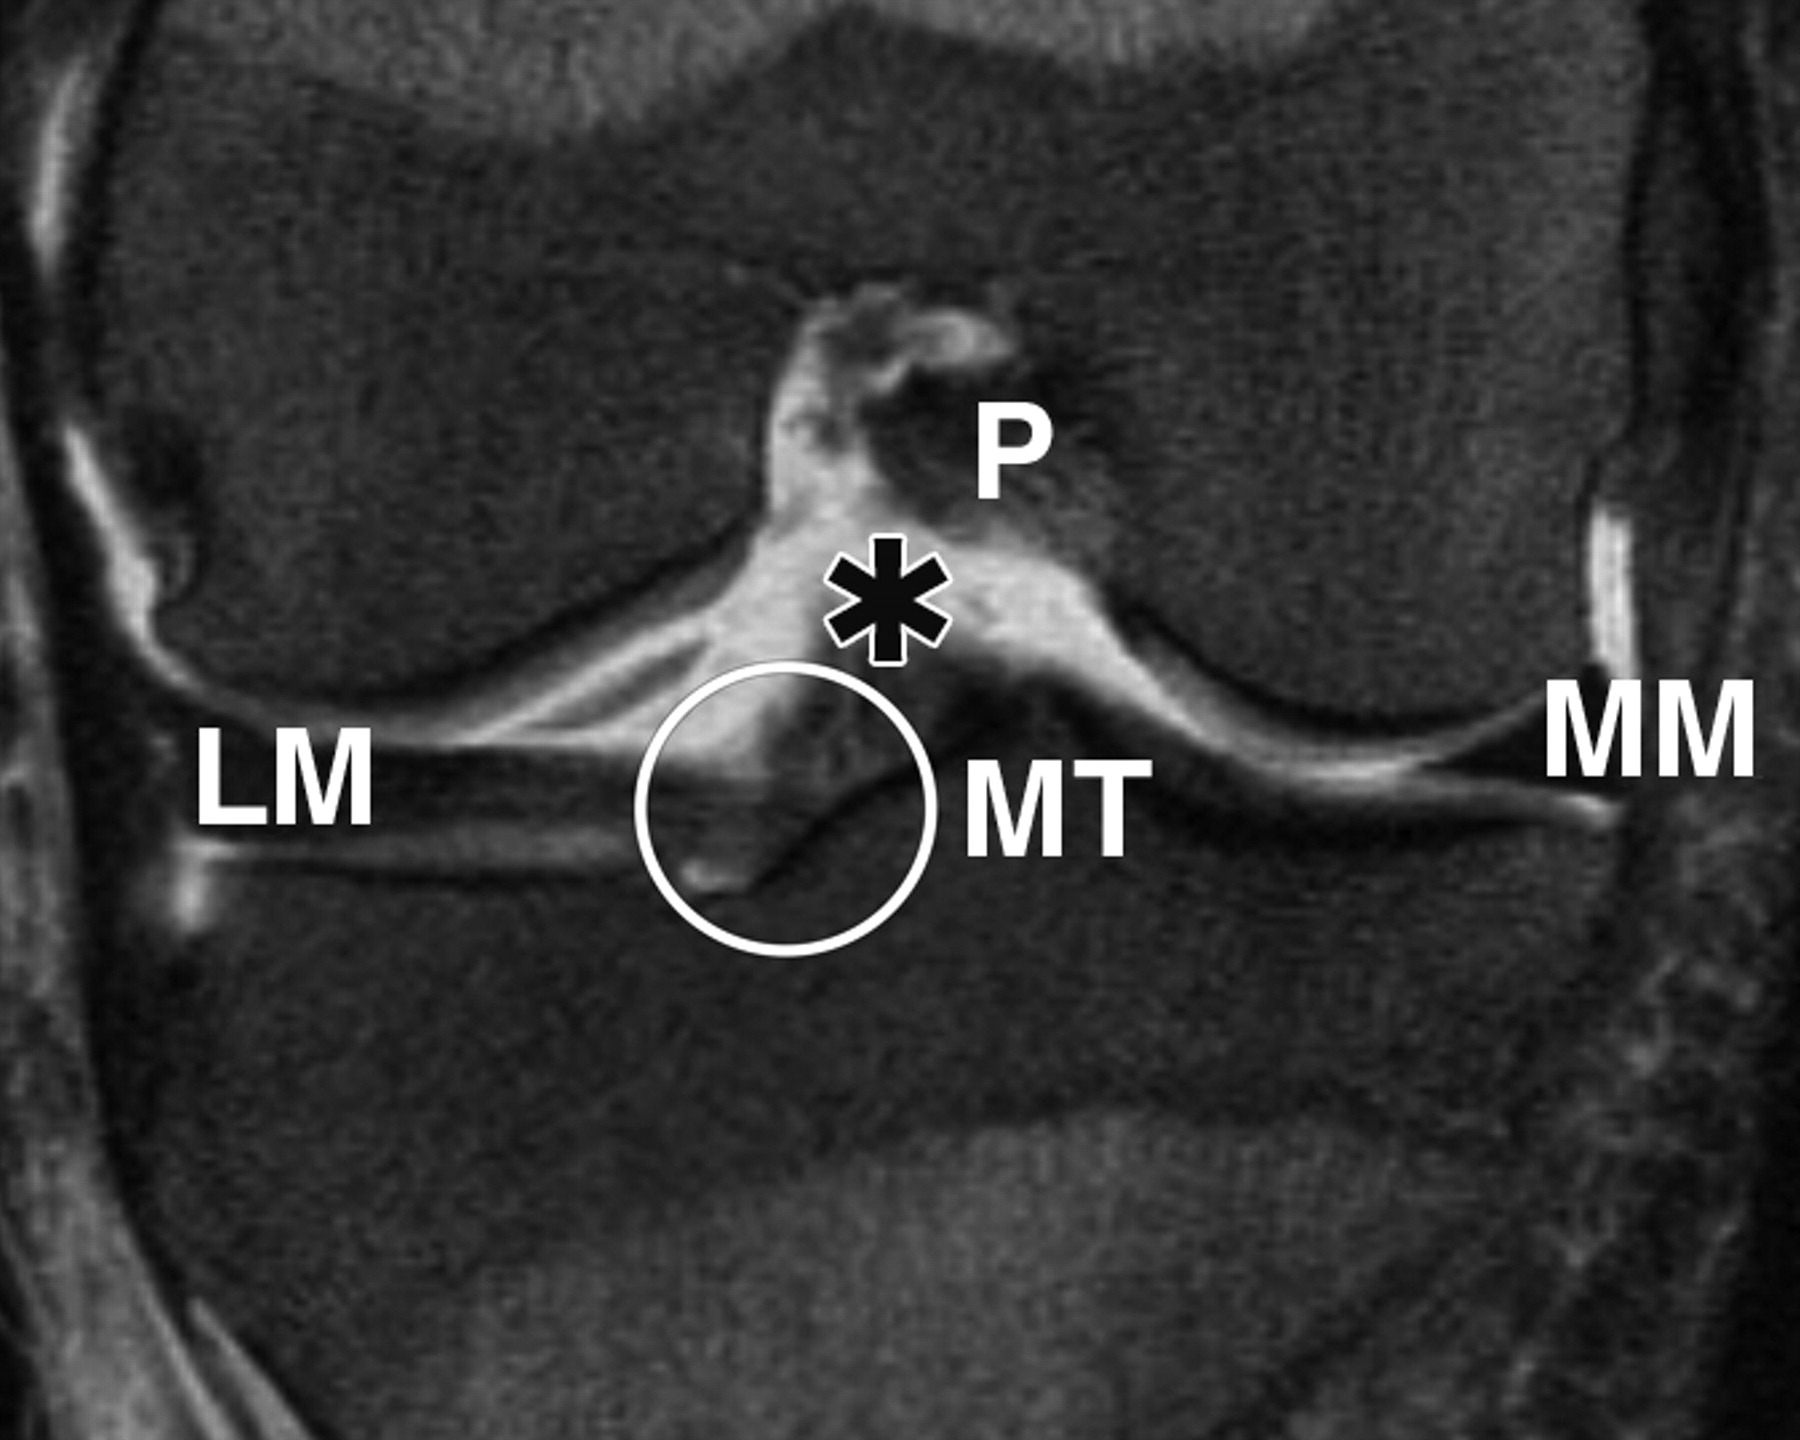

c72f940e7a2b62d20ba7c9ccc9eff2c3.jpeg

图3B-51岁女性。

膝关节的中等加权、脂肪饱和、快速自旋回波(TR/TEeff,3,700/29)3-T MR图像显示了膝关节前根、前交叉韧带(ACL)和膝横韧带的解剖关系。相对于A的后部冠状位MR图像显示内侧胫骨结节(MT)外侧斜面上外侧半月板(LM)前根的附着点(圆圈)接近ACL胫骨附着点(星号)。P =后交叉韧带,MM =内侧半月板。